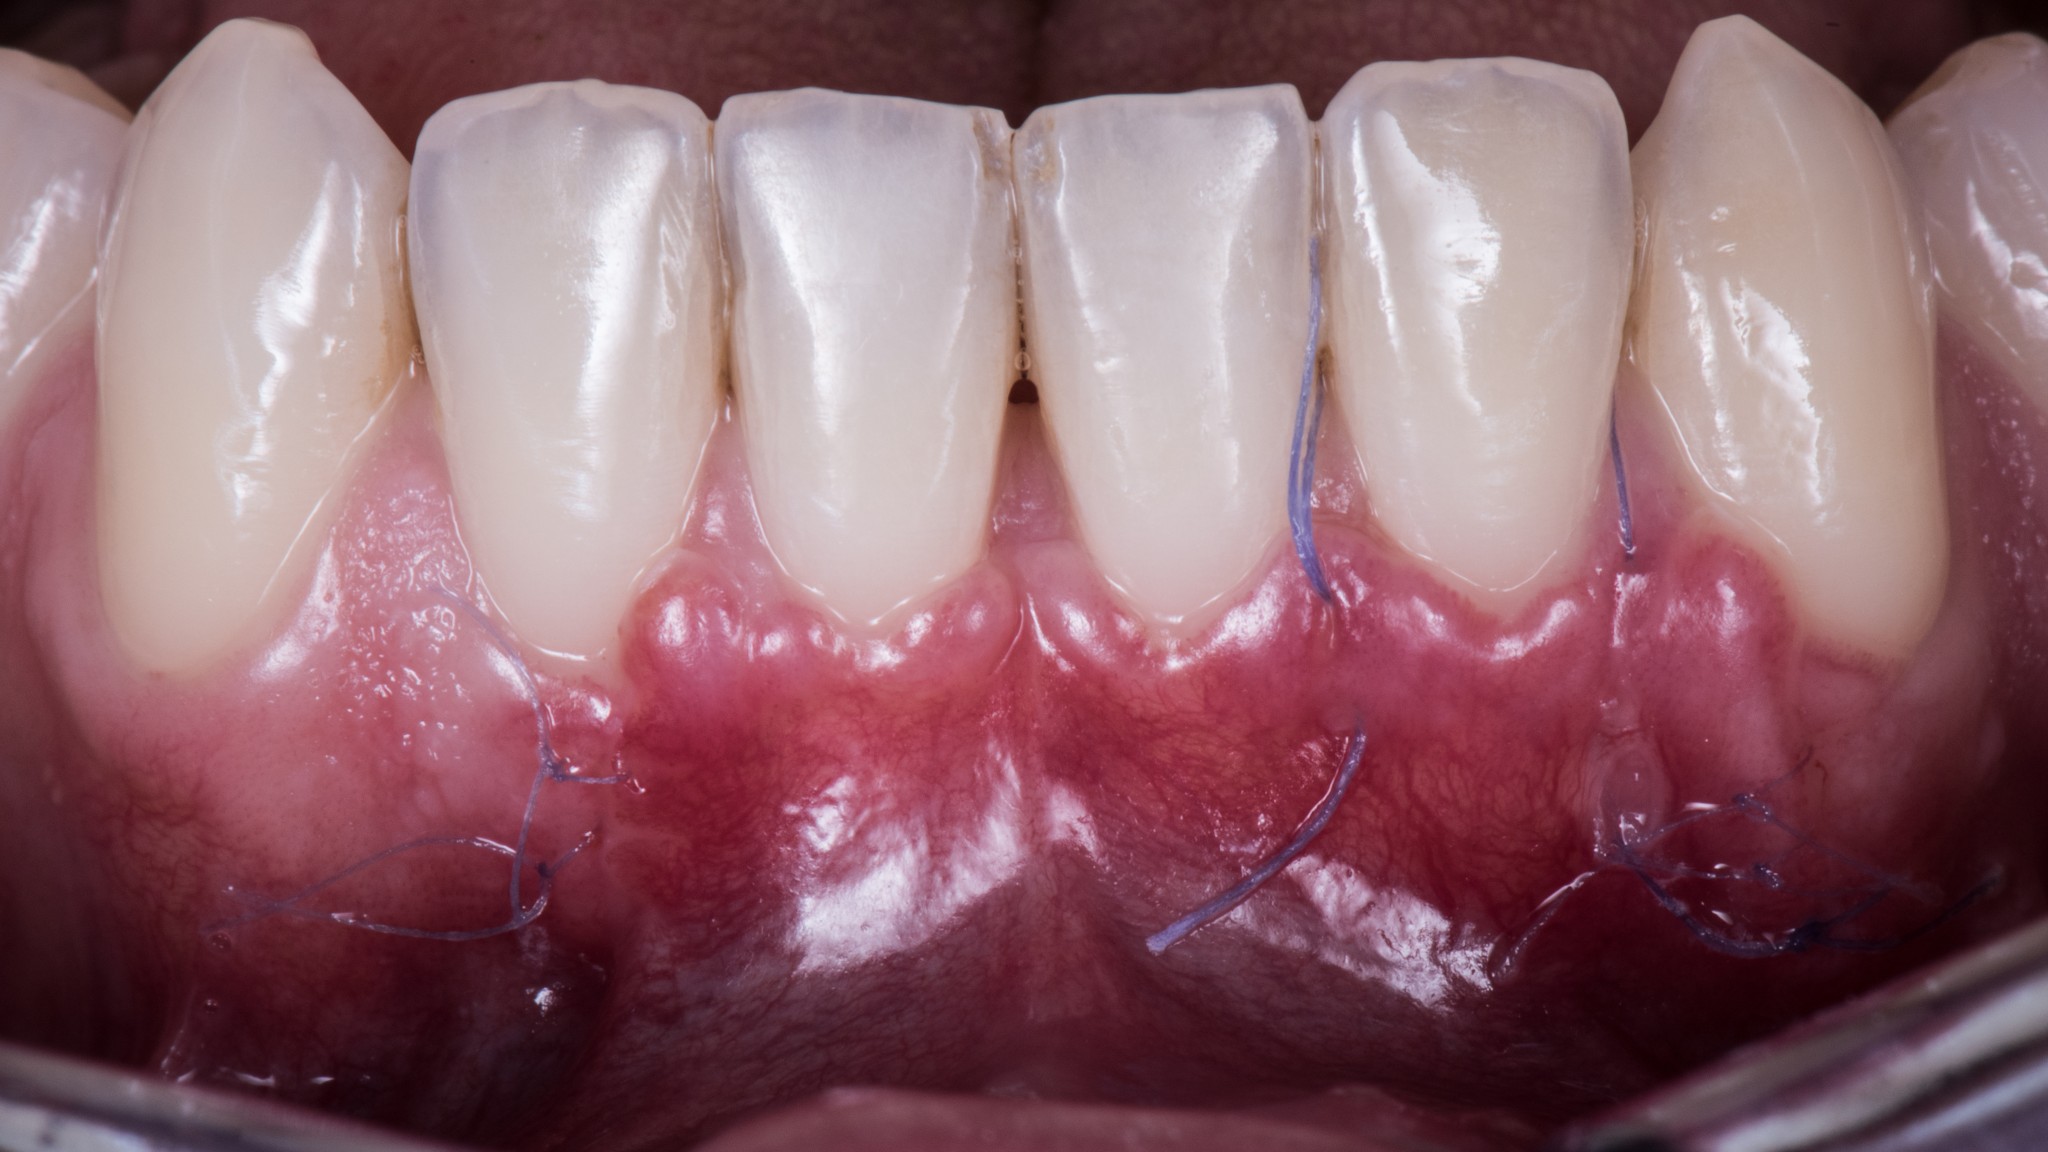

Questo, associato alle altre due tecniche segrete di cui parleremo nei prossimi articoli, ti consente di arrivare a 15 giorni dall’intervento in questa situazione:

Ma soprattutto di arrivare a 3 mesi in questa:

Nonostante lo spostamento coronale di circa 5 mm le inserzioni muscolari e il frenulo sono esattamente nella stessa posizione di prima. Il fatto che ci sia uno slivellamento della linea mucogengivale è un’ovvia conseguenza dell’intervento, quella non la possiamo evitare, ma ci penserà la Natura. Ancora qualche mese e tutto tornerà a posto da solo.

Non si vede bene?!

Hai ragione. Ti faccio un’altra foto:

Le vedi adesso le inserzioni? ?